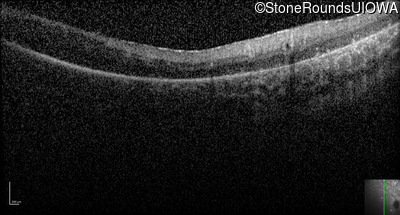

Optical Coherence Tomography - Right -

No Light Perception

Exemplar

Expanded OCT Stack

×